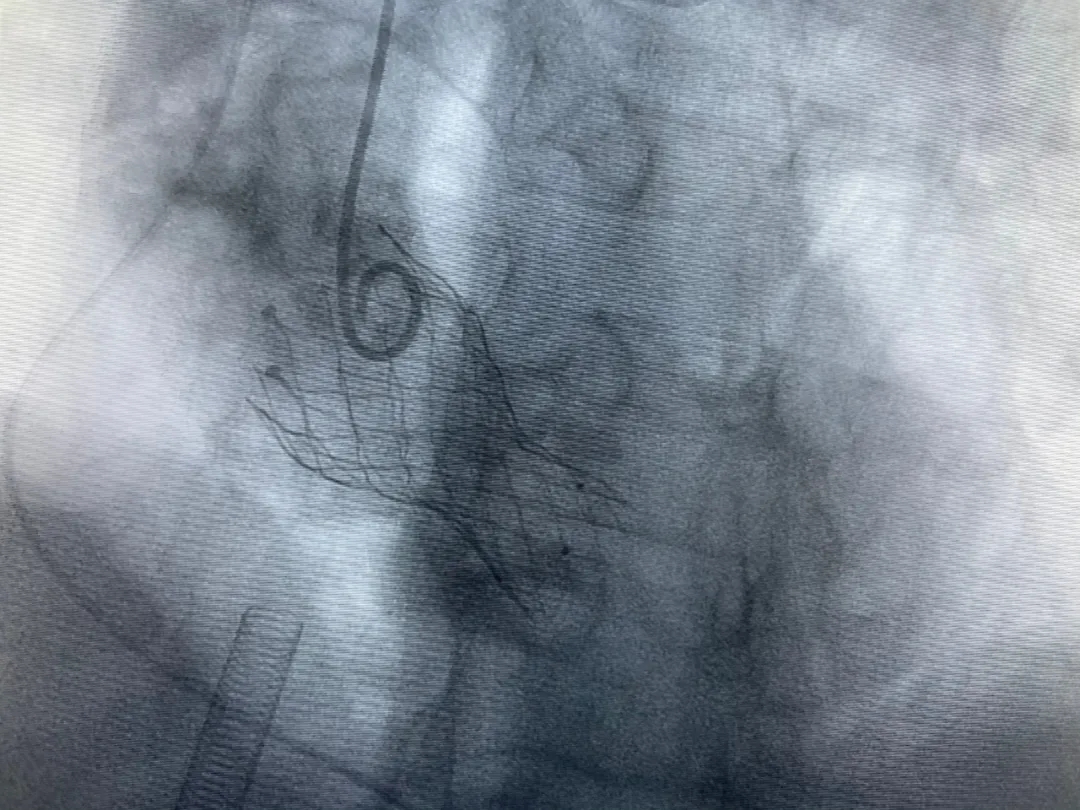

結(jié)合老人病情特點:年齡高、室壁厚、左室腔小、瓣膜鈣化嚴重,術(shù)中球囊擴張和瓣膜釋放過程有循環(huán)崩潰可能;為降低此種風險、最大程度提高手術(shù)成功率,張金洲副院長在術(shù)前組織了由楊金保博士帶領(lǐng)的TAVR團隊多次反復溝通、討論,制定了各種應(yīng)急處理方案。最終經(jīng)過TAVR團隊的默契配合,手術(shù)歷時2小時,用20#球囊預(yù)擴張后順利植入23#主動脈瓣生物瓣膜,再次后擴后主動脈根部造影顯示:人工主動脈瓣生物瓣位置良好,瓣葉開閉正常;冠脈顯影良好。經(jīng)食道超聲顯示:主動脈瓣葉活動度良好,主動脈跨瓣壓差約35mmHg,未見瓣周漏及明顯返流。出手術(shù)室前老人便已蘇醒,自訴憋悶癥狀完全消失。